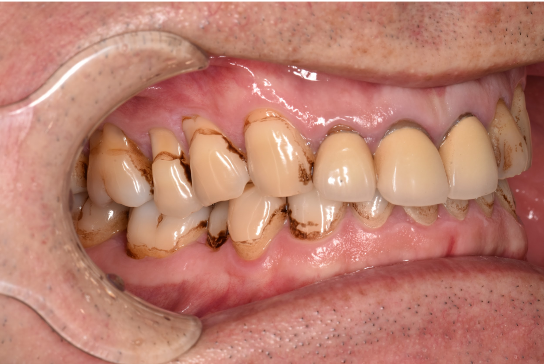

治療前

| カウンセリング・診断結果 | ご相談通り、全体的に着色と歯石が付着していました。歯周病の検査を行ったところ全体的に歯周病が進行しており、中等度~重度の歯周炎が認められました。 |

| 行ったご提案・治療内容 | 初診時に撮影したレントゲン、口腔内写真、歯周検査の結果を用いて、着色除去、歯周病治療の必要性をお伝えしました。 初診時は歯ブラシのお話しをさせていただき、セルフケアの方法について説明を行い、その後気にされてみえた着色除去、歯肉縁上歯石除去を行いましました。 歯肉の炎症がある程度落ち着いたところで、後日、再評価を行い歯周治療へ移行しました。 |